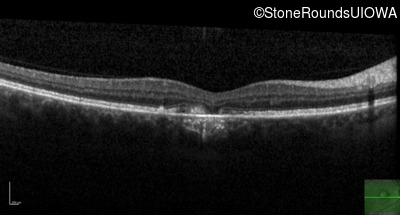

Pattern Dystrophy (IIC)

Age at visit: 51 years

This 51 year old woman first noticed some metamorphopsia in her left eye in her early 30's.

Pattern Dystrophy PRPH2 IVS2+3 A>T   AD